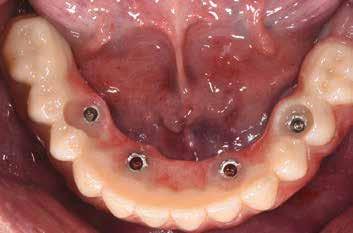

Bevezetés

Az azonnali, implantátumokkal megtámasztott teljes íves fogpótlások jól bevált, és egyre inkább elfogadott kezelési módot képviselnek a teljesen fogatlan betegek rehabilitációjában.1,2 Az ilyen típusú helyreállítások esetében átlagosan 5 éves követési időszakban 98%os túlélési arányról számoltak be.3 Az alsó állkapocs kedvező csontminőségnek és anatómiának köszönhetően az azonnali teljes ívek helyreállítása még nagyobb sikerarányt mutatott.4 A digitális technológiák, mint például a sablonnal végzett implantátumbeültetés és a számítógéppel segített protézistervezés és gyártás, képesek megkönnyíteni a diagnózist, a kezelés megtervezését és jelentősen javítják a sebészeti beavatkozásokat, ezáltal kiszámíthatóbb és hatékonyabb kezelést biztosítanak.5,6 Különösen a bonyolult sebészeti eljárások – mint például a teljes ív rekonstrukciója – jelentős mértékben profitálhatnak ezekből az előnyökből, amelyek csökkenthetik a kezelés idejét és az invazivitást a beteg számára.5,7

A digitális technológiákhoz való hozzáférést az anyagi és időkorlátok akadályozhatják, valamint az ilyen technológiákhoz kapcsolódó meredek tanulási görbe.8,9 A közelmúltban a digitális munkafolyamatok elérhetővé váltak egy kihelyezett szolgáltatás részeként: Smile in a Box (Straumann). Ez segíthet a hagyományos munkafolyamatokat használó szakembereknek, hogy könnyen élvezhessék a digitális technológiák előnyeit anélkül, hogy először le kellene küzdeniük az első hozzáféréssel járó akadályokat. Ez az esettanulmány egy hagyományos teljes fogsor sikeres azonnali átalakítását írja le azonnali teljes ívű restaurációvá a Smile in a Box által biztosított kiszervezett, teljesen digitális munkafolyamat alkalmazásával. A Straumann Pro Arch protokoll alkalmazása a Smile in a Box funkcióval kombinálva lehetővé tette számunkra, hogy könnyen hozzáférhessünk egy teljesen digitális munkafolyamathoz, amely hatékonyan integrálható a hagyományos protetikai munkafolyamatunkba, továbbá rendkívül kielégítő klinikai eredményt biztosít.

Klinikánkon egy teljesen fogatlan, hagyományos akrilát fogpótlással helyreállított 65 éves férfi beteg jelentkezett, aki nem kielégítő alsó fogsorretencióra és az azzal járó problémákra panaszkodott, beleértve a kifejezetten az alsó fogsorához kapcsolódó gyenge beszéd és rágásfunkciót. A klinikai vizsgálat gömbölyűtől a késhegyig terjedő mandibulagerinc formát és megfelelő vertikális, de nem megfelelő vízszintes csontmennyiséget állapított meg, különösen a hátsó területen (1. ábra) 10

A diagnosztikai panoráma röntgenfelvételen a mandibula íve mérsékelt IIIIV. osztályú atrófiával és megfelelő térfogatú, viszonylag sűrű III. típusú kortikális csonttal jelentkezett az interforaminális területen (2. ábra).

A betegnek jól kontrollált 2es típusú cukorbetegsége és jól kontrollált magas vérnyomása volt. Nem azonosítottak olyan

témás vagy lokális kockázati tényezőket vagy ellenjavallatokat, amelyek kizárták volna a pácienst az implantációs kezelésből. A különböző kezelési lehetőségekről, azok előnyeiről és korlátairól szóló alapos megbeszélést követően a páciens egy implantátumokon megtámasztott alsó fogsort kombinálva egy új, hagyományos felső teljes kivehető fogpótlást részesített előnyben.

A hagyományos teljes kivehető fogpótlási technikákkal a kezelési stratégia a felső és alsó állcsont kapcsolatának és az okkluzális vertikális dimenzió és a fog helyzetének meghatározását foglalta magában, majd az alsó rögzített restauráció előállításához ezeket használták fel referenciákként (3. ábra) 11